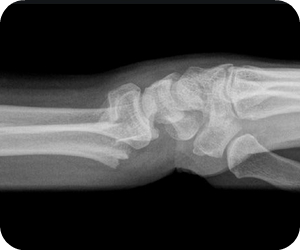

Estudio sobre las formas y el funcionamiento de las diferentes estructuras del cuerpo humano, estudios por imágenes para obtener imágenes del interior de su cuerpo, se pueden usar para diagnosticar y tratar enfermedades y lesiones. Los tejidos de su cuerpo cambian los patrones de energía para producir una imagen o fotografía.